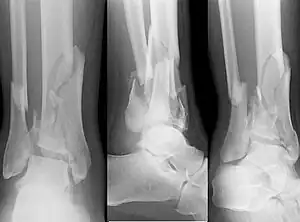

Fracture of both sides of the ankle with dislocation as seen on anteroposterior X-ray. (1) fibula, (2) tibia, (arrow) medial malleolus, (arrowhead) lateral malleolus

On X-rays, there can be a fracture of the medial malleolus, the lateral malleolus, or of the anterior/posterior margin of the distal tibia. [17] If both the lateral and medial malleoli are broken, this is called a bimalleolar fracture[18]. If the posterior malleolus is also fractured, this is called a trimalleolar fracture. [19]